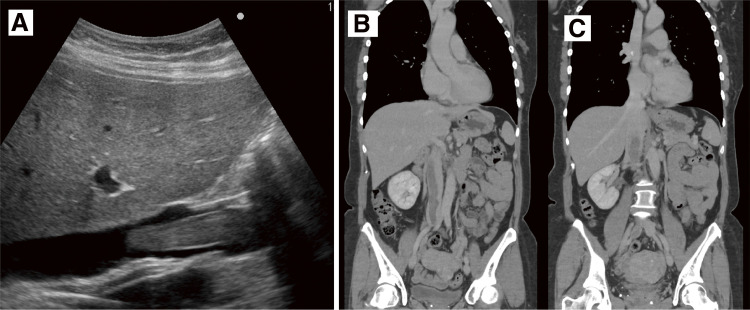

静脉平滑肌瘤病(IVL)仍然很少报道,完全切除肿瘤是推荐的治疗方法。在此,我们提出了一个全面的审查的情况下,52岁的妇女谁遭受复发性晕厥发作由于IVL心内延伸到右心房。先行肿瘤部分切除及术后激素治疗。然而,术后6个月随访的计算机断层扫描显示IVL有增大的趋势,因此进行了完全切除。在本文中,我们想强调的是,部分切除后激素治疗是不够的IVL,应选择完全切除。

Intravenous leiomyomatosis (IVL) remains scarcely reported, and complete tumor resection is the recommended treatment. Herein, we present a comprehensive review of the case of a 52-year-old woman who suffered from recurrent syncope episodes due to IVL with intracardiac extension to the right atrium. Partial tumor resection and postoperative hormone therapy were conducted first. However, the 6-month postoperative follow-up computed tomography scan revealed a tendency for the IVL to increase in size, and complete resection was conducted. In this article, we would like to emphasize that partial resection followed by hormone therapy is insufficient for IVL, and complete resection should be chosen.